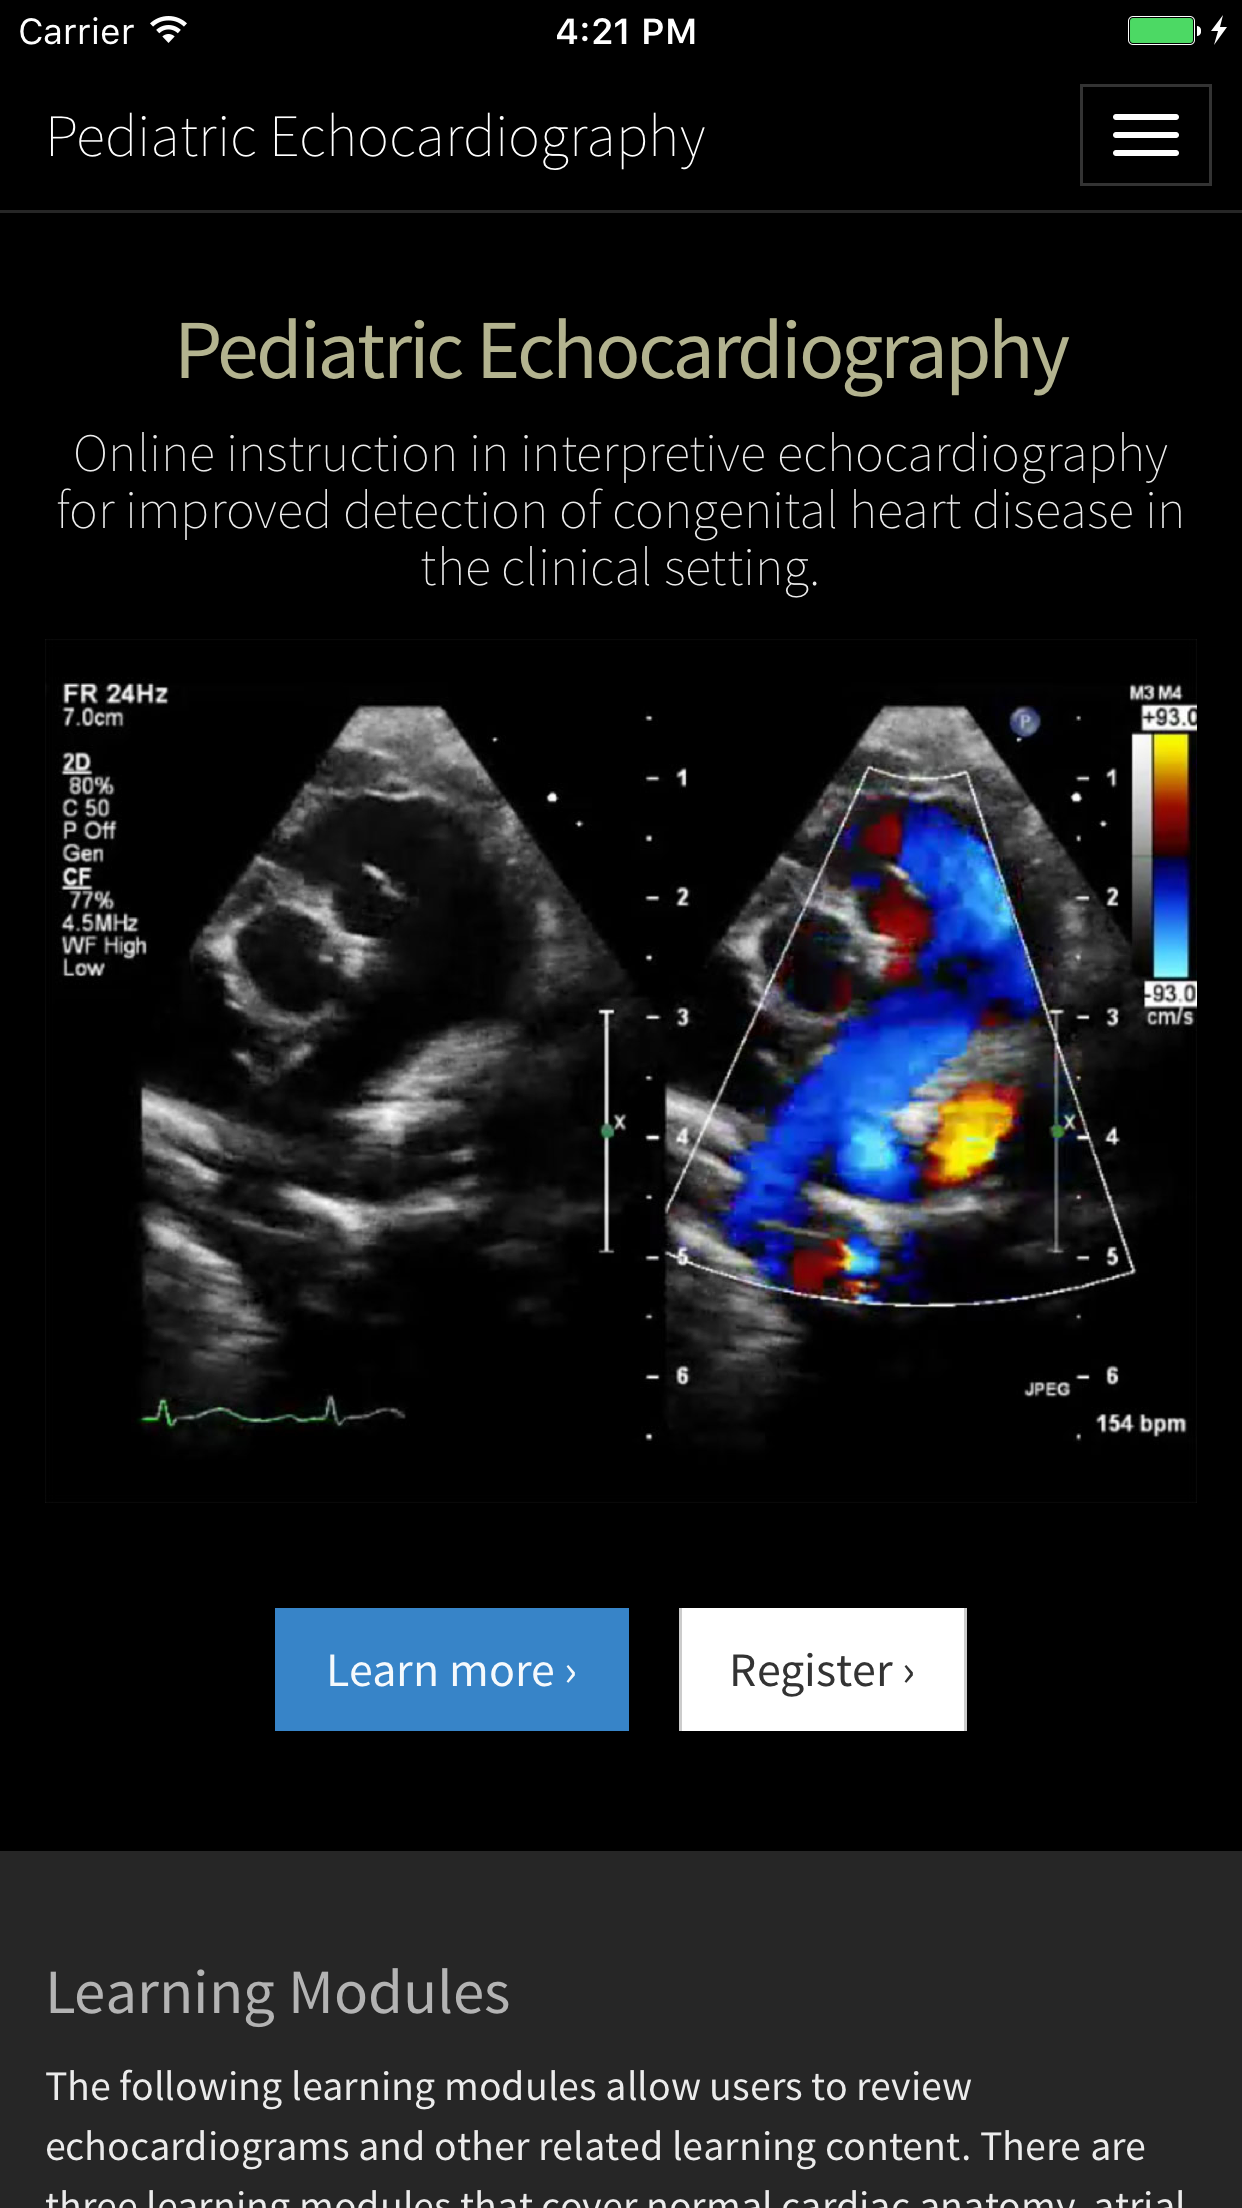

Echocardiography has become an essential technology and is utilized by the majority of pediatric cardiologists. It serves as an indispensible tool in the diagnosis and treatment of congenital heart disease. It involves mastering a complex skill set made up of two key components: procedural echocardiography and interpretive echocardiography. The goal of this app is to provide a background in interpretive echocardiography in the setting of basic and complex congenital heart disease. Congenital heart disease (CHD) is a spectrum of disease from a small hole in the heart to very complex congenital abnormalities. Training physicians and sonographers in echocardiography is a challenge. Cardiologists are expected to not only master a procedural skill, but they are also faced with the challenging task of interpreting those images. Because some types of CHD are quite rare, it is often difficult for trainees in smaller institutions to get exposed to these rare variants. *** Educational Objectives *** - To provide comprehensive training in interpretive echocardiography. - To expose trainees to all variants of congenital heart disease and their subtypes. - To provide a better understanding of normal echocardiographic anatomy. - To allow an interactive approach to reviewing and identifying echocardiographic examples of normal anatomy and congenital heart disease. - To ultimately allow for better identification of cardiac pathology in the clinical setting. *** Target Audience *** This app is meant to serve as an learning resource for medical students, residents, cardiology fellows, cardiologists and sonographers. It provides a comprehensive echo imaging database of fetal and transthoracic echocardiography. In addition, three introductory learning modules (normal anatomy, atrial septal defects and ventricular septal defects) are offered along with with pre and post testing to assess the user’s baseline knowledge and improvement following completion of the learning modules. All answers and scores on the pre and post test are provided to the user upon completion of the post test (the post test becomes available once all views from all three modules have been viewed).